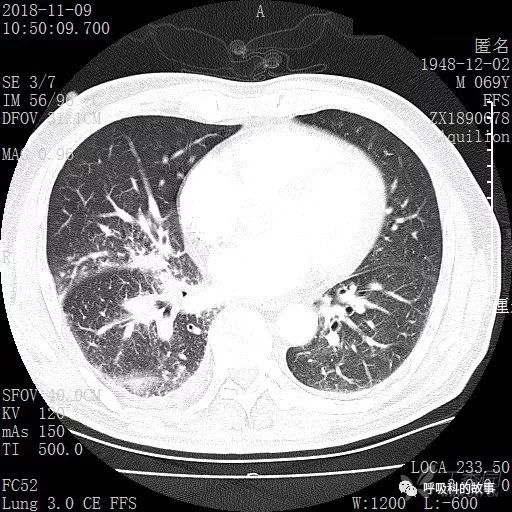

胸部增强CT示右肺门占位伴远端阻塞性肺炎,纵膈、右肺门、右侧颈根部、右侧腋下及肝门部肿大淋巴结。两侧胸腔少量积液。

肺窗CT